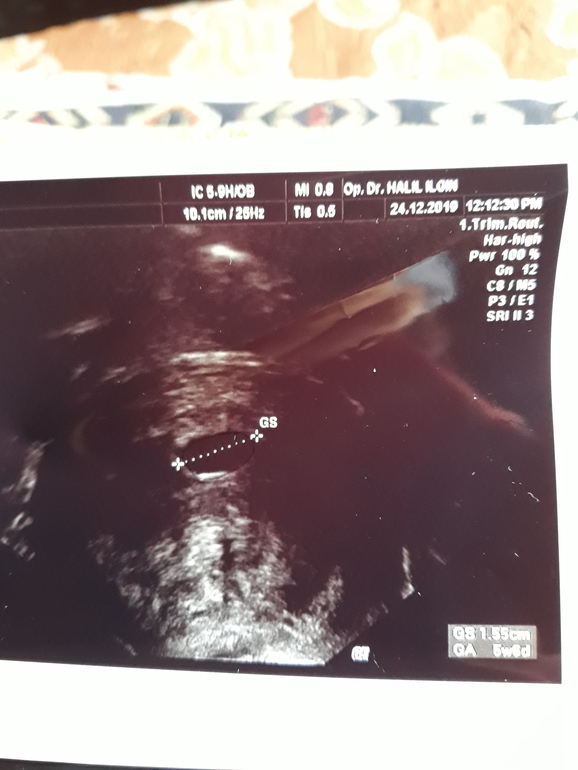

Эмбрион?

Эмбрион будет в правом верхнем углу на желточном мешочке, наверно, за пунктиром измерения его не видно😊 всё хорошо, всё на месте! Через недельку услышите сердечко. У меня при пя 16мм тоже не было эмбриона, через 4 дня уже был)

Это не эмбрион... но я вижу желточный мешочек справа вверху. Скорее всего, поздняя овуляция. У меня сначала также было, через неделю эмбрион и сердечко.

Я не вижу ничего в верхнем правом углу. Врач сказал что эмбрион он нашел, эмбрион формируется, сердцебиения пока еще нет.

А врач померил его? Я вижу только размер ПЯ

Да он сказал это эмбрион, но вот я не пойму почему он так странно выглядит

Тоже отставание на неделю. В 6.3 по акушерскому сроку по фото только пя

7 недель срок. Я помню снимки с прошлых беременностей. Там был эмбрион а тут линия какая-то. Врач сказал эмбрион есть ну вот я ничего не вижу кроме линии

Врач сказал эмбрион на 6 недель развит а я в упор ничего не вижу, неужели вот эта белая черта?

Я пришла сначала к одному врачу тот вообще ничего не увидел,.абсолютно пустая матка. Все отлично говорит. Но я же не дура как может быть все отлично при пустой матке. Второй врач хороший смотрел смотрел говорит нашел эмбрион, сердца пока нет, ждет через неделю. Я пью дюфастон думаю пить или бросать и ждать пока само все выйдет. Срок 7 недель